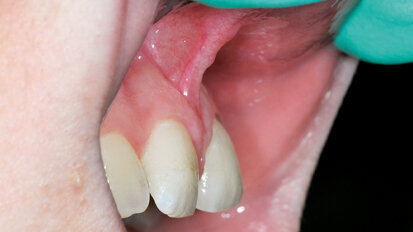

Rehabilitace Straumann